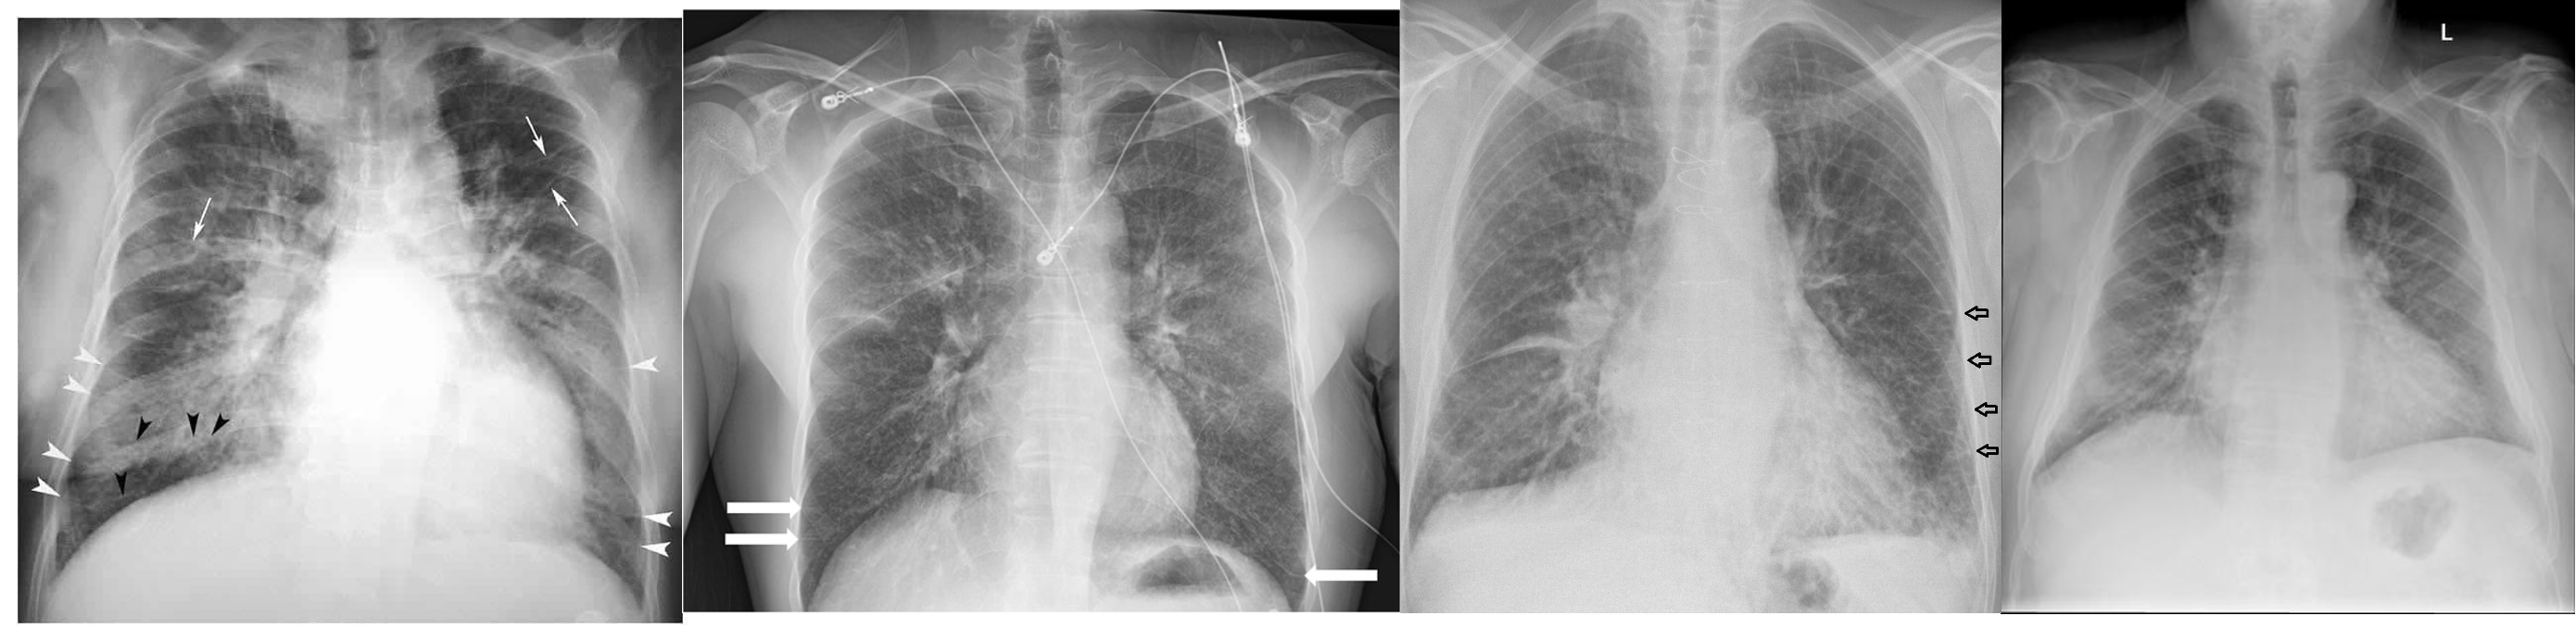

(Image: Cardiomegaly & pulmonary edema)

Cardiomegaly & pulmonary edema

- Chest X ray:

- Cardiomegaly

- Pulmonary edema

- Pleural effusion

Kerly B lines( interstitial edema)

Prominent blood vessels in upper lung field (called cephali sation)

How to calculate Cardiomegaly Horizontal diameter of the heart divided by widest horizontal distance in the chest cavity. If more than 0.5 ⇒ cardiomegaly (How to remember: heart/chest)